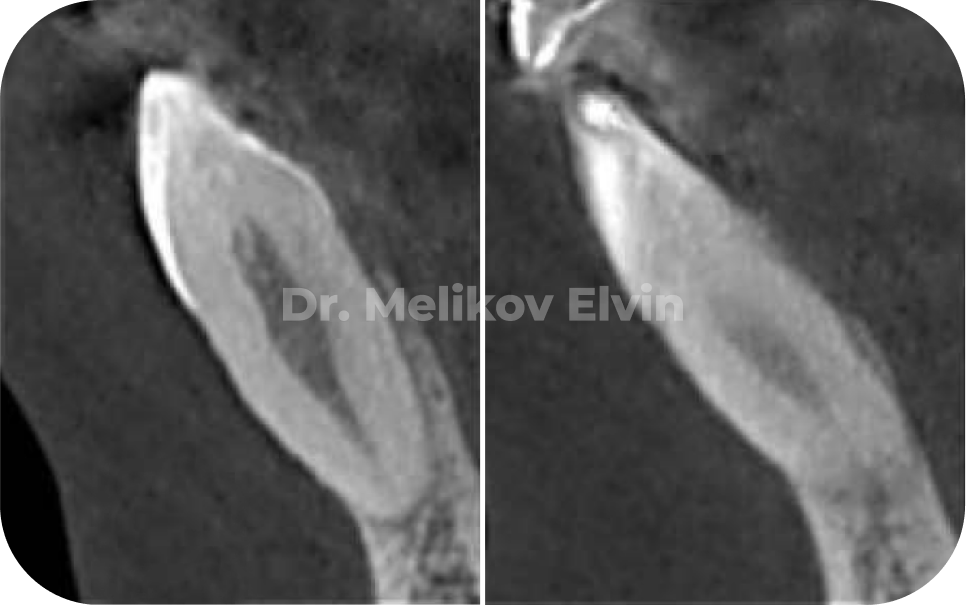

До костной пластики.

После костной пластики.